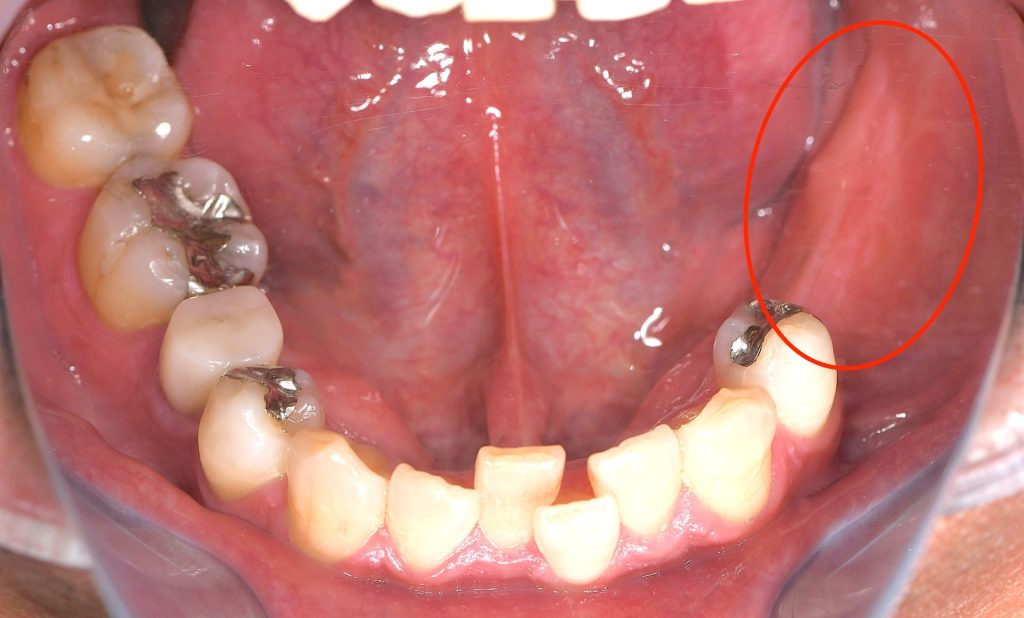

来院時の口腔内の状態と診断

検診希望にて来院。

左下7(第二大臼歯)は、歯根破折により数年前に他院で抜歯済み。

左下6(第一大臼歯)は、過去に近心根の歯根破折に対して

歯根分割抜歯(ヘミセクション)が行われており、遠心根のみ残存している状態。

欠損部位は、左下5(第二小臼歯)および左

下6遠心根を支台歯としたブリッジ補綴により修復されていた。

左下5・左下6遠心根ともに、歯質量・歯周組織の状態から、

長期的予後としては良好とは言えない状態であることを説明。

ただし現時点では保存可能と判断し、安易な抜歯は行わず、「可能な限り歯を残す方針」について

患者さんと共有し、経過観察・管理を行う方針とした。

初回来院後、定期的に検診・メンテナンスで来院されていたが、

初回来院から約1年後、左下5番に自発痛を認めた。

診査の結果、元々咬合力が非常に強く、う蝕により歯質が菲薄化(薄く脆弱化)した状態の歯牙が

咬合負荷に耐えきれず、歯根破折を発症していることを確認。

また、左下6遠心根についても構造的・機能的予後が不良と判断。

来院時の口腔内写真